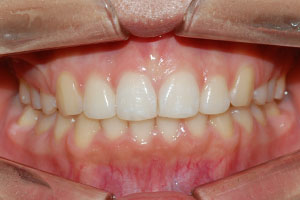

치료증례 전후사진

Before & After